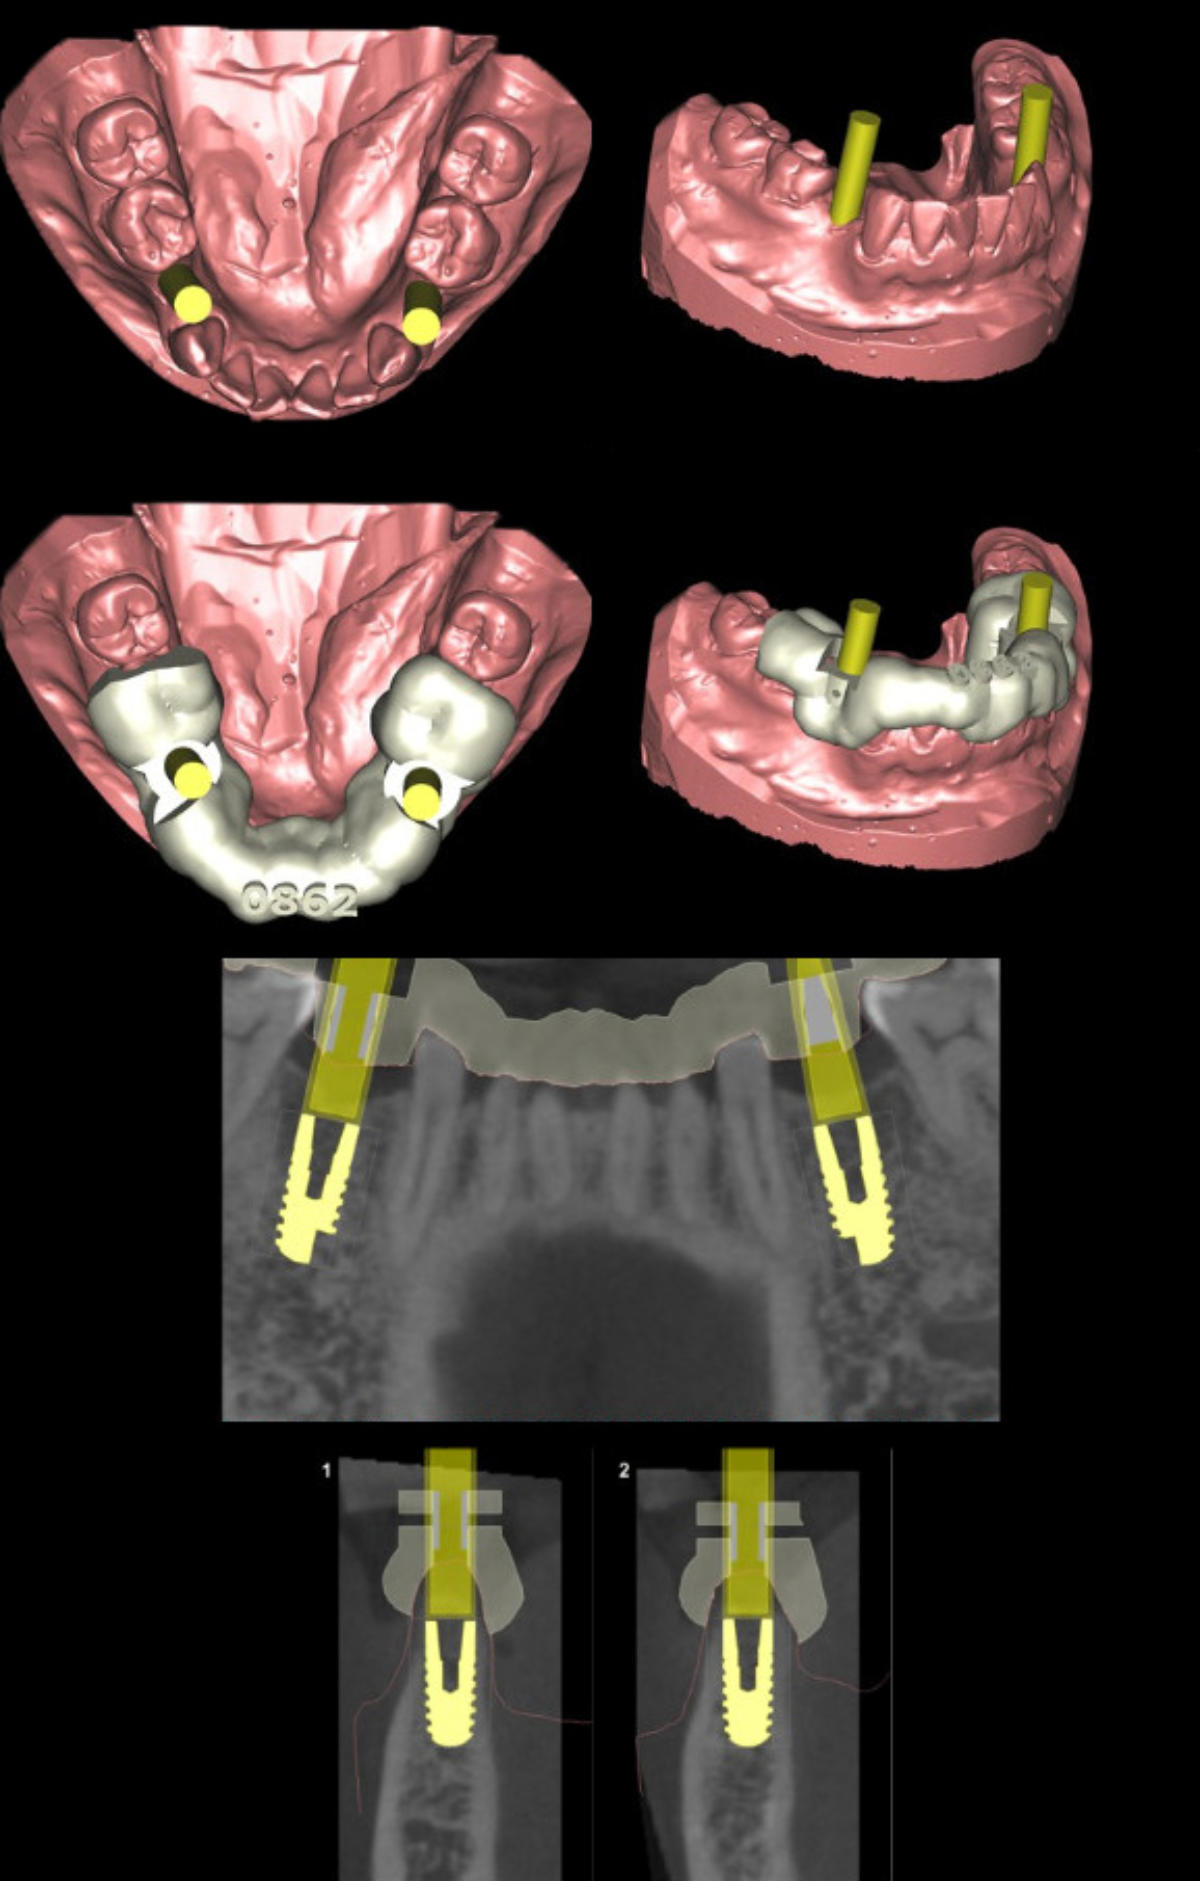

An Hand von vorliegenden dreidimensionalen Befunddaten ( 3D- Röntgenbild -DVT/ digitalisiertes Kiefermodell) wird vor dem eigentlichen Eingriff am Computer mit einer speziellen Software eine virtuelle Implantation durchgeführt ( Simulation der geplanten Operation) und auf Basis der ermittelten Daten eine Bohrschablone für das Setzen der späteren Implanate in Auftrag gegeben. Vorteile des Verfahrens sind : klinische Umsetzung und Reproduzierbarkeit der gewünschten Implantatpositionen Ermittlung des eventuell erforderlichen Bedarfs an knochenaufbauenden (augmentativen) Maßnahmen maximale Schonung benachbarter anatomischer Strukturen vor unbeabsichtigter Verletzung (Nachbarzähne, im Operationsgebiet verlaufende Nerven, Kieferhöhle etc.) Umsetzung der in der virtuellen Planung in funktioneller und ästhetischer Sicht als optimal ermittelten Implantatposition ; die individuelle intraoperative Korrekturmöglichkeit bleibt jeder- zeit gegeben Verkürzung des operativen Eingriffs durch die präoperative Operationsplanung

umfangreiche virtuelle Operationsplanung 3-D Implantatplanung Operationsschablone - angefertigt  nach virtueller Implantation umfangreiche virtuelle Operationsplanung umfangreiche virtuelle Operationsplanung

Virtuelle Implantation (Operationsplanung) am Computer